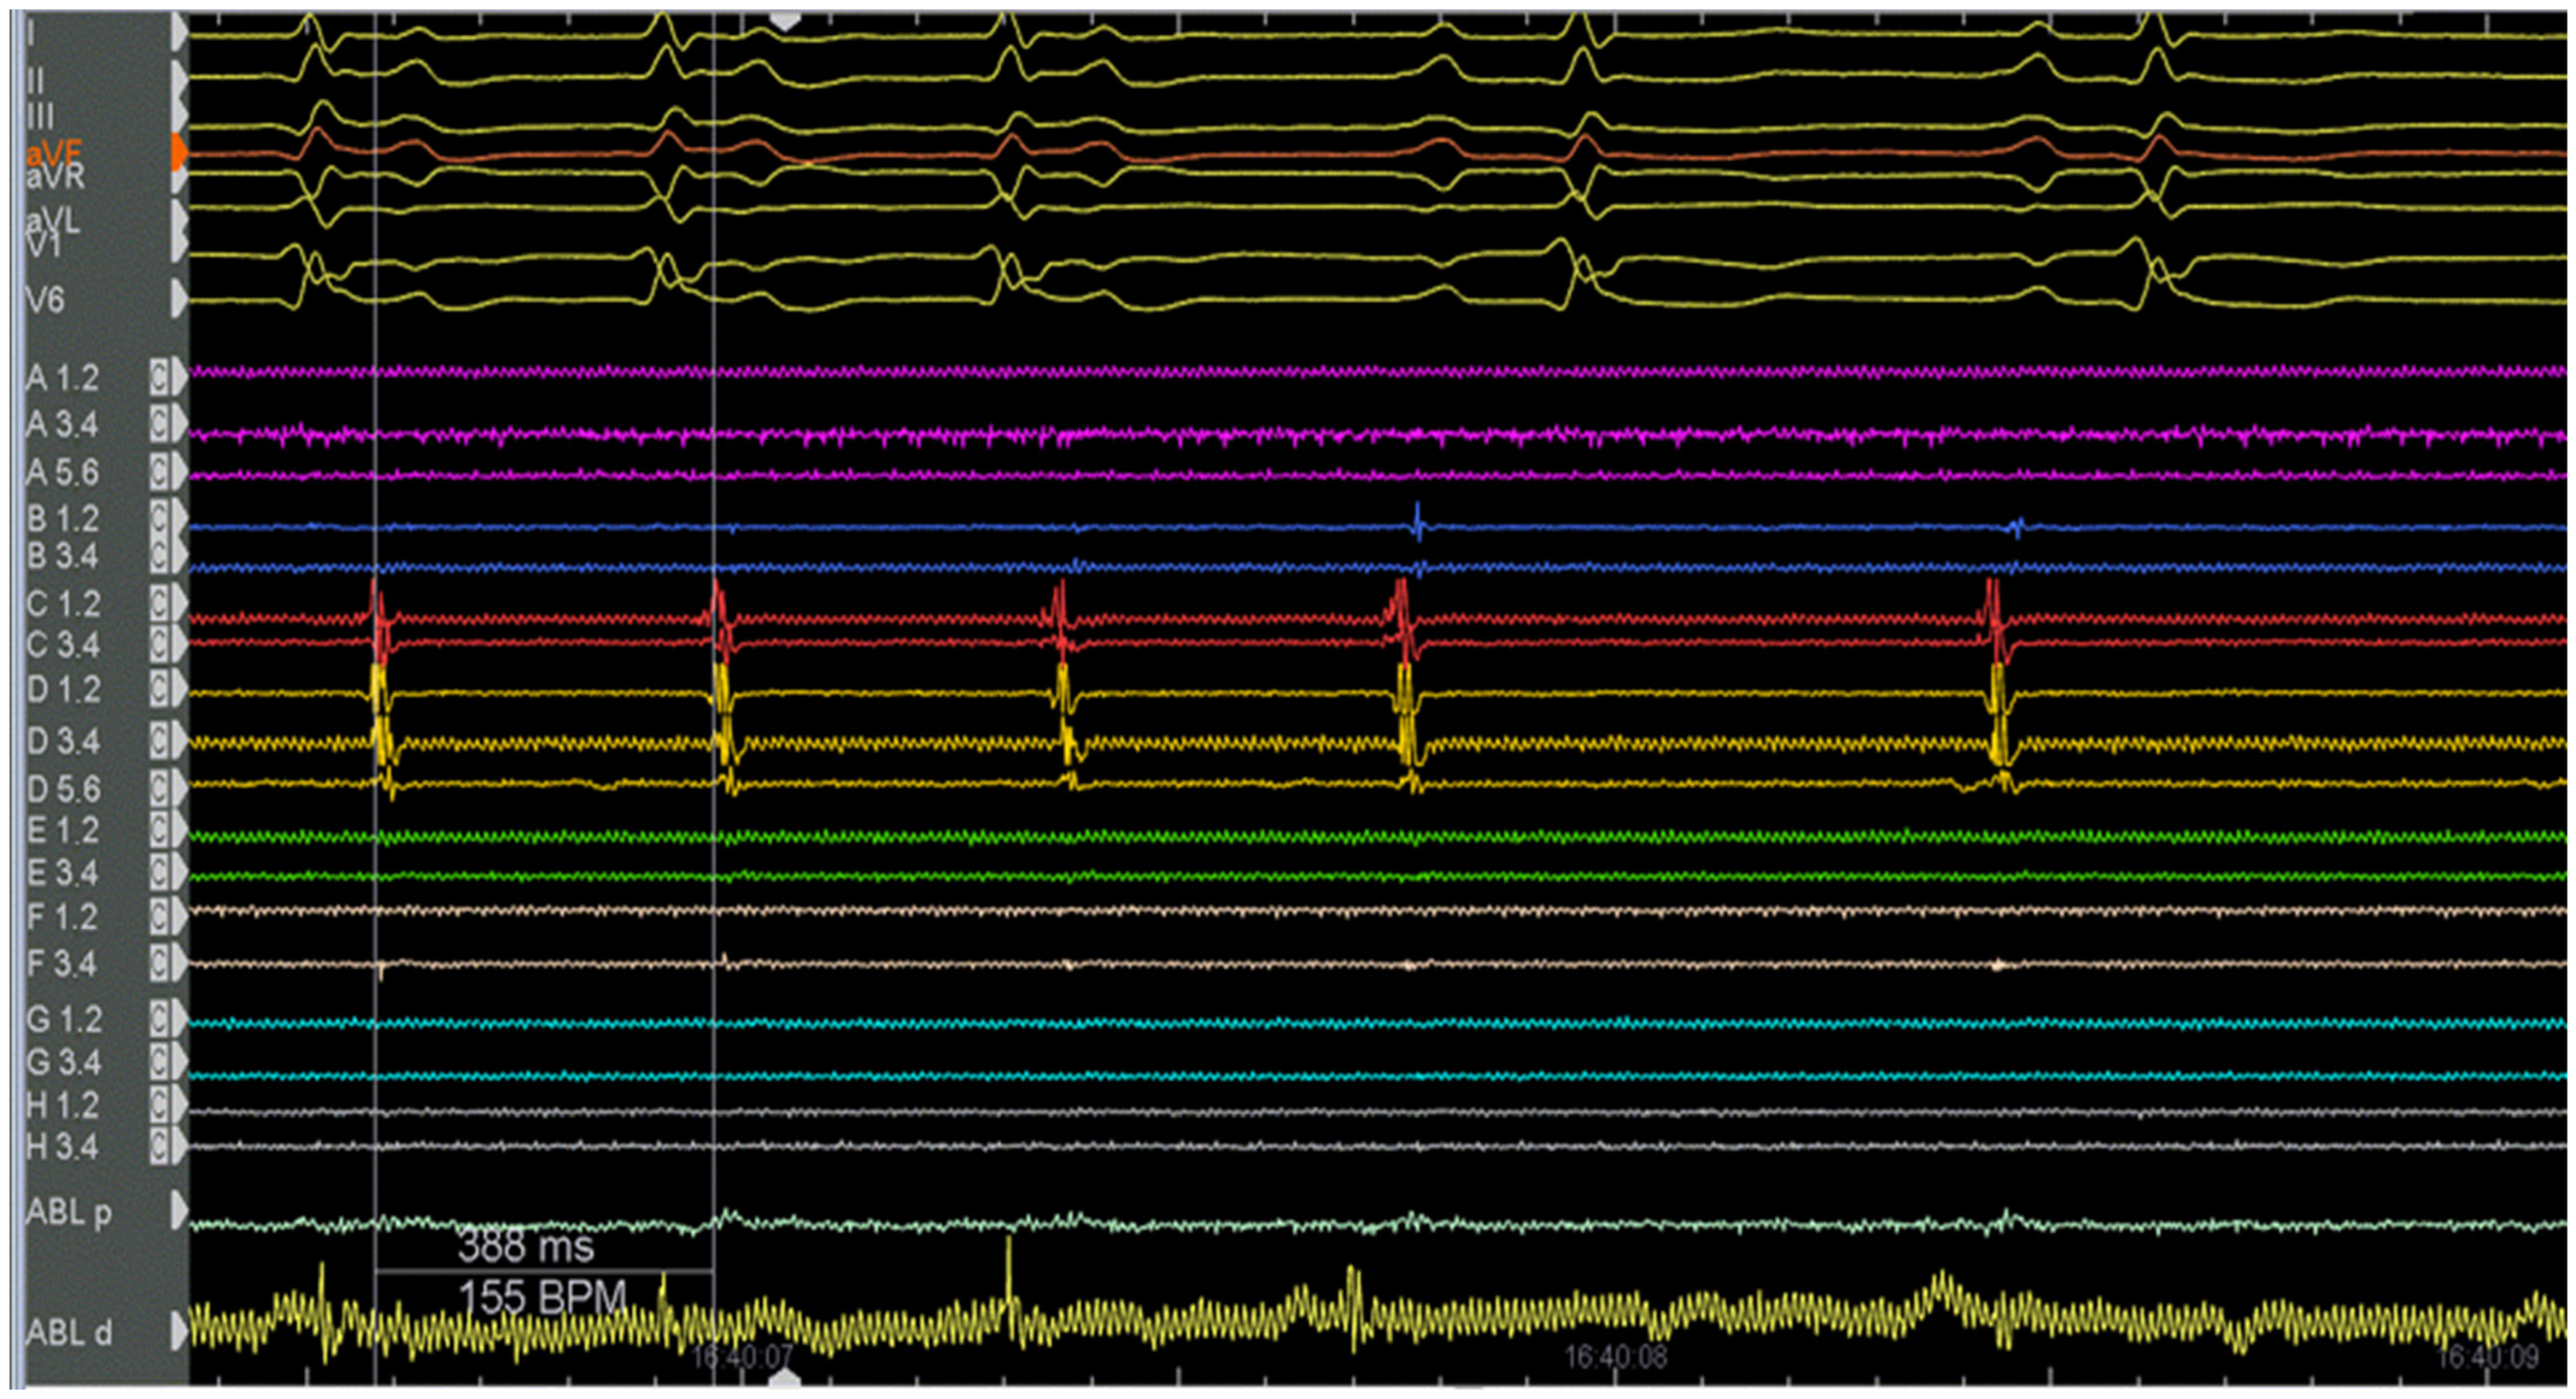

2. Case Description